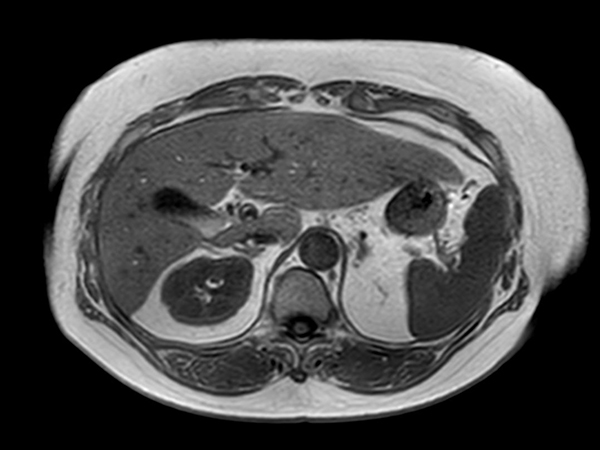

T2w TSE (single shot)

MR Elastography (SE-EPI, 4 slices)